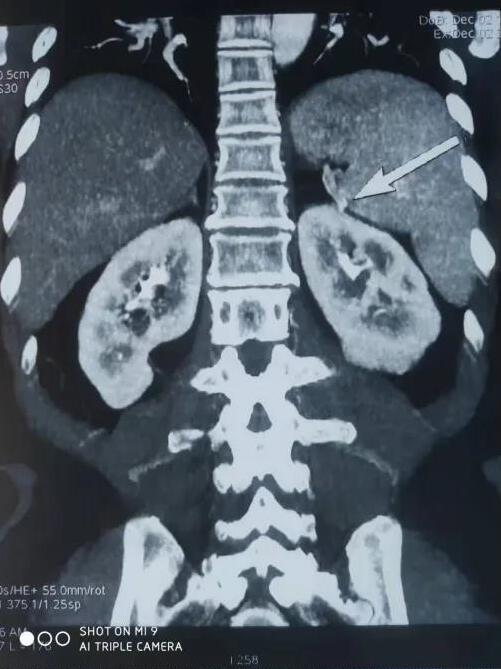

患者,女性,61岁,因体检发现左肾肿物一周收入院,入院后行全腹部增强CT检查回报:左肾下极肿瘤。大小48*47mmhg,肿瘤分期:T1bM0N0,肿瘤位于肾实质深部,上极紧贴肾门,各期影像显示患肾血供复杂:包括肾动脉、副肾动脉各一支。

肾静脉两支

变异血管分布如下:

第四腰椎椎前血管发出的侧支动脉一支

穿过后腹膜入肾上极变异动脉一支(来源于脾动脉)

肿瘤回流静脉一支(内有癌栓)